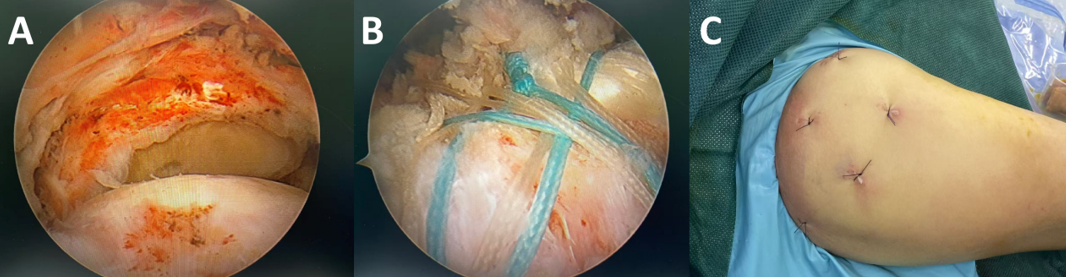

肩关节镜下肩袖修补术 A:镜下见肩袖巨大撕裂,肌腱回缩,肱骨头完裸露。B:双排缝合桥技术修补肩袖巨大撕裂,修补后肌腱完全覆盖肱骨头。C:术后伤口。

次日,钟名金博士主刀、李兴福博士担任助手,在关节镜下精准实施,开5个0.5cm的小口子(比指甲盖还小),借助高清镜头松解粘连、精准缝合,全程才1小时,出血居然不到10ml!相较于传统开放手术,关节镜技术具有创伤小、恢复快、并发症少等优势,最大程度保留肩关节周围软组织功能。术后第二天阿姨就能在医师指导下活动、训练,肩痛直接缓解大半!